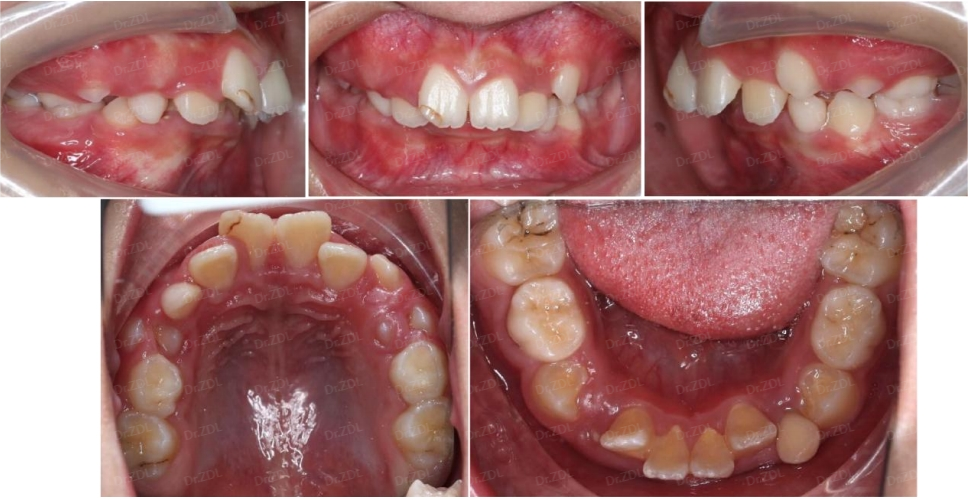

Grace硅胶牙套案例2:

这位6岁小朋友,主诉牙凸,临床检查看上前牙III度深覆合深覆盖,上颌牙弓狭窄,牙齿存在散在间隙。

早期矫正方案利用好孩子替牙期的生长发育潜力,结合孩子的牙齿情况和面型情况,制作Grace个性化定制硅胶牙套佩戴。

佩戴 Grace12 个月,上下颌牙弓形态恢复正常,牙齿排齐良好,上前牙角度恢复良好,前牙咬合打开良好,前牙正常覆合覆盖。